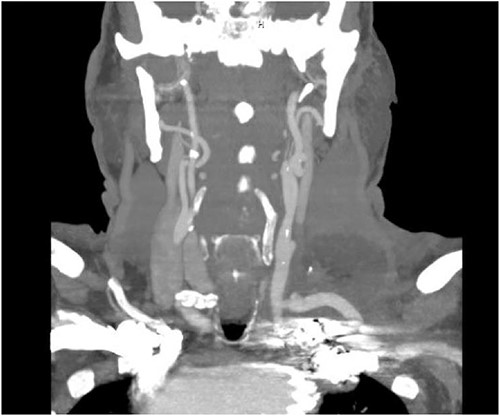

The patient’s post-operative course was uneventful, and he was discharged home on post-operative day 6 from the initial operation and on post-operative day 3 from TEVAR. CT angiography done prior to discharge revealed successful exclusion of the left SAA without endoleak and a patent left common carotid to left subclavian bypass and transposed left vertebral artery (Fig. 5). The patient had repeat imaging 3 months post-procedure that again redemonstrated the above findings.

CT angiogram showing patency of the left carotid to subclavian artery bypass graft with vertebral artery implantation and showing coil embolization of the proximal left SAA.